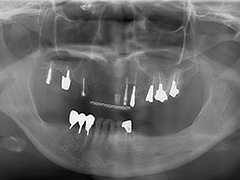

Case.10 コーヌスクローネ義歯症例(装着後10年経過)

他院で歯がグラグラ動いて咬み合わせも決まらないから全部歯を抜いて総義歯治療をすすめられた患者さん。

初診時

年齢層 | 60代 女性 |

どんなお悩み | 他院で歯がグラグラ動いて咬み合わせも決まらないから全部歯を抜いて総義歯治療をすすめられた患者さん。保存不可能な歯を抜いて、残ってる歯に二重に冠をかぶせて入れ歯をとめる義歯を制作(コーヌスデンチャー)磁性アタッチメントも併用しています。 |

治療 期間 | 治療期間は4か月程度 |